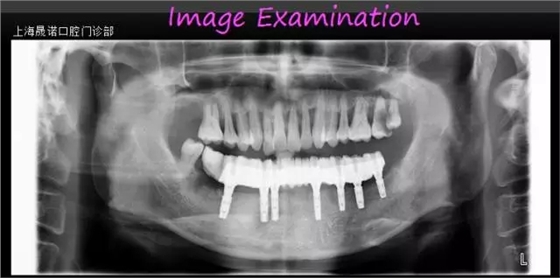

男46歲 患者主訴: 下頜牙缺損伴疼痛,無法滿足日常飲食需求,要求修復(fù)。 診斷: 牙列缺損,中晚期牙周炎。 治療方案: (1)確定終修復(fù):種植體支持的全牙弓一體式 CAD/CAM全鈦烤塑復(fù)合橋。 (2)種植外科前面弓轉(zhuǎn)移,確定咬合關(guān)系。 (3)根據(jù)R2GATE制作標(biāo)準(zhǔn)拍攝CBCT。 (4)R2GATE種植方案確定及生成。 (5) 種植外科:結(jié)合臨床條件及R2GATE植入EZPlus,鎖定八角基臺。 (6)即刻負(fù)重:被動性印模,當(dāng)日完成種植體支持的螺絲固位臨時橋修復(fù)體。 (7)終修復(fù):依據(jù)患者臨時橋修復(fù)體的佩戴情況,評估及完成終修復(fù)。終修復(fù)為全牙弓一體式CAD/CAM全鈦烤塑復(fù)合橋。 (8)隨訪和專業(yè)口腔衛(wèi)生維護(hù):第一次3個月;第二次半年~一年。放射對照性檢查為每年一次。 術(shù)前口內(nèi)檢查 術(shù)前影像檢查分析 種植位點設(shè)計 種植位點評估 R2GATE導(dǎo)航系統(tǒng)設(shè)計種植體分別為 右下4:EZplus 4*11.5mm; 右下6:EZPlus 4.5*10mm; 左下5:EZPlus 4*10mm; 左下6:EZPlus 4.5*10mm; 左下7:EZPlus 4.5*7mm. R2種植導(dǎo)板 收到R2GATE導(dǎo)板及手術(shù)報表,導(dǎo)板外科工具盒。 治療步驟 第二周9:30-11:30:摘除R2GATE,33、43即拔即種。拔除34、44、45、46;口內(nèi)就位R2GATE,44、46、35、36、37不翻瓣導(dǎo)航下完成全程備洞。 35(EZPlus 4.0*10mm) 36(EZPlus 4.5*10mm) 37(EZPlus 4*8.5mm) 33、43(EZPlus 4.0*13mm) 44(EZPlus 4.0*11.5mm) 46(EZPlus 4.5*10mm) 植入扭力都大于50Ncm,分別35N鎖定八角基臺,并用手?jǐn)Q緊八角愈合帽,將骨引導(dǎo)材料(Bio-Oss,Geistlich)植入骨缺損區(qū)。